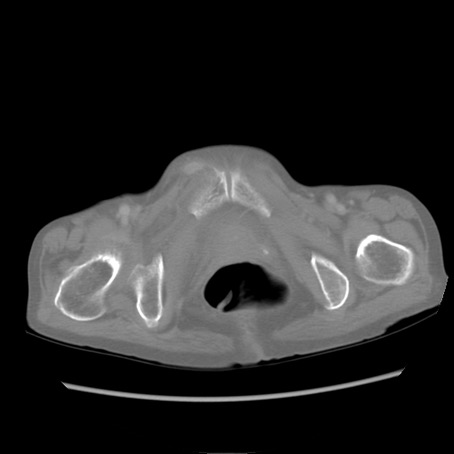

冠状断像